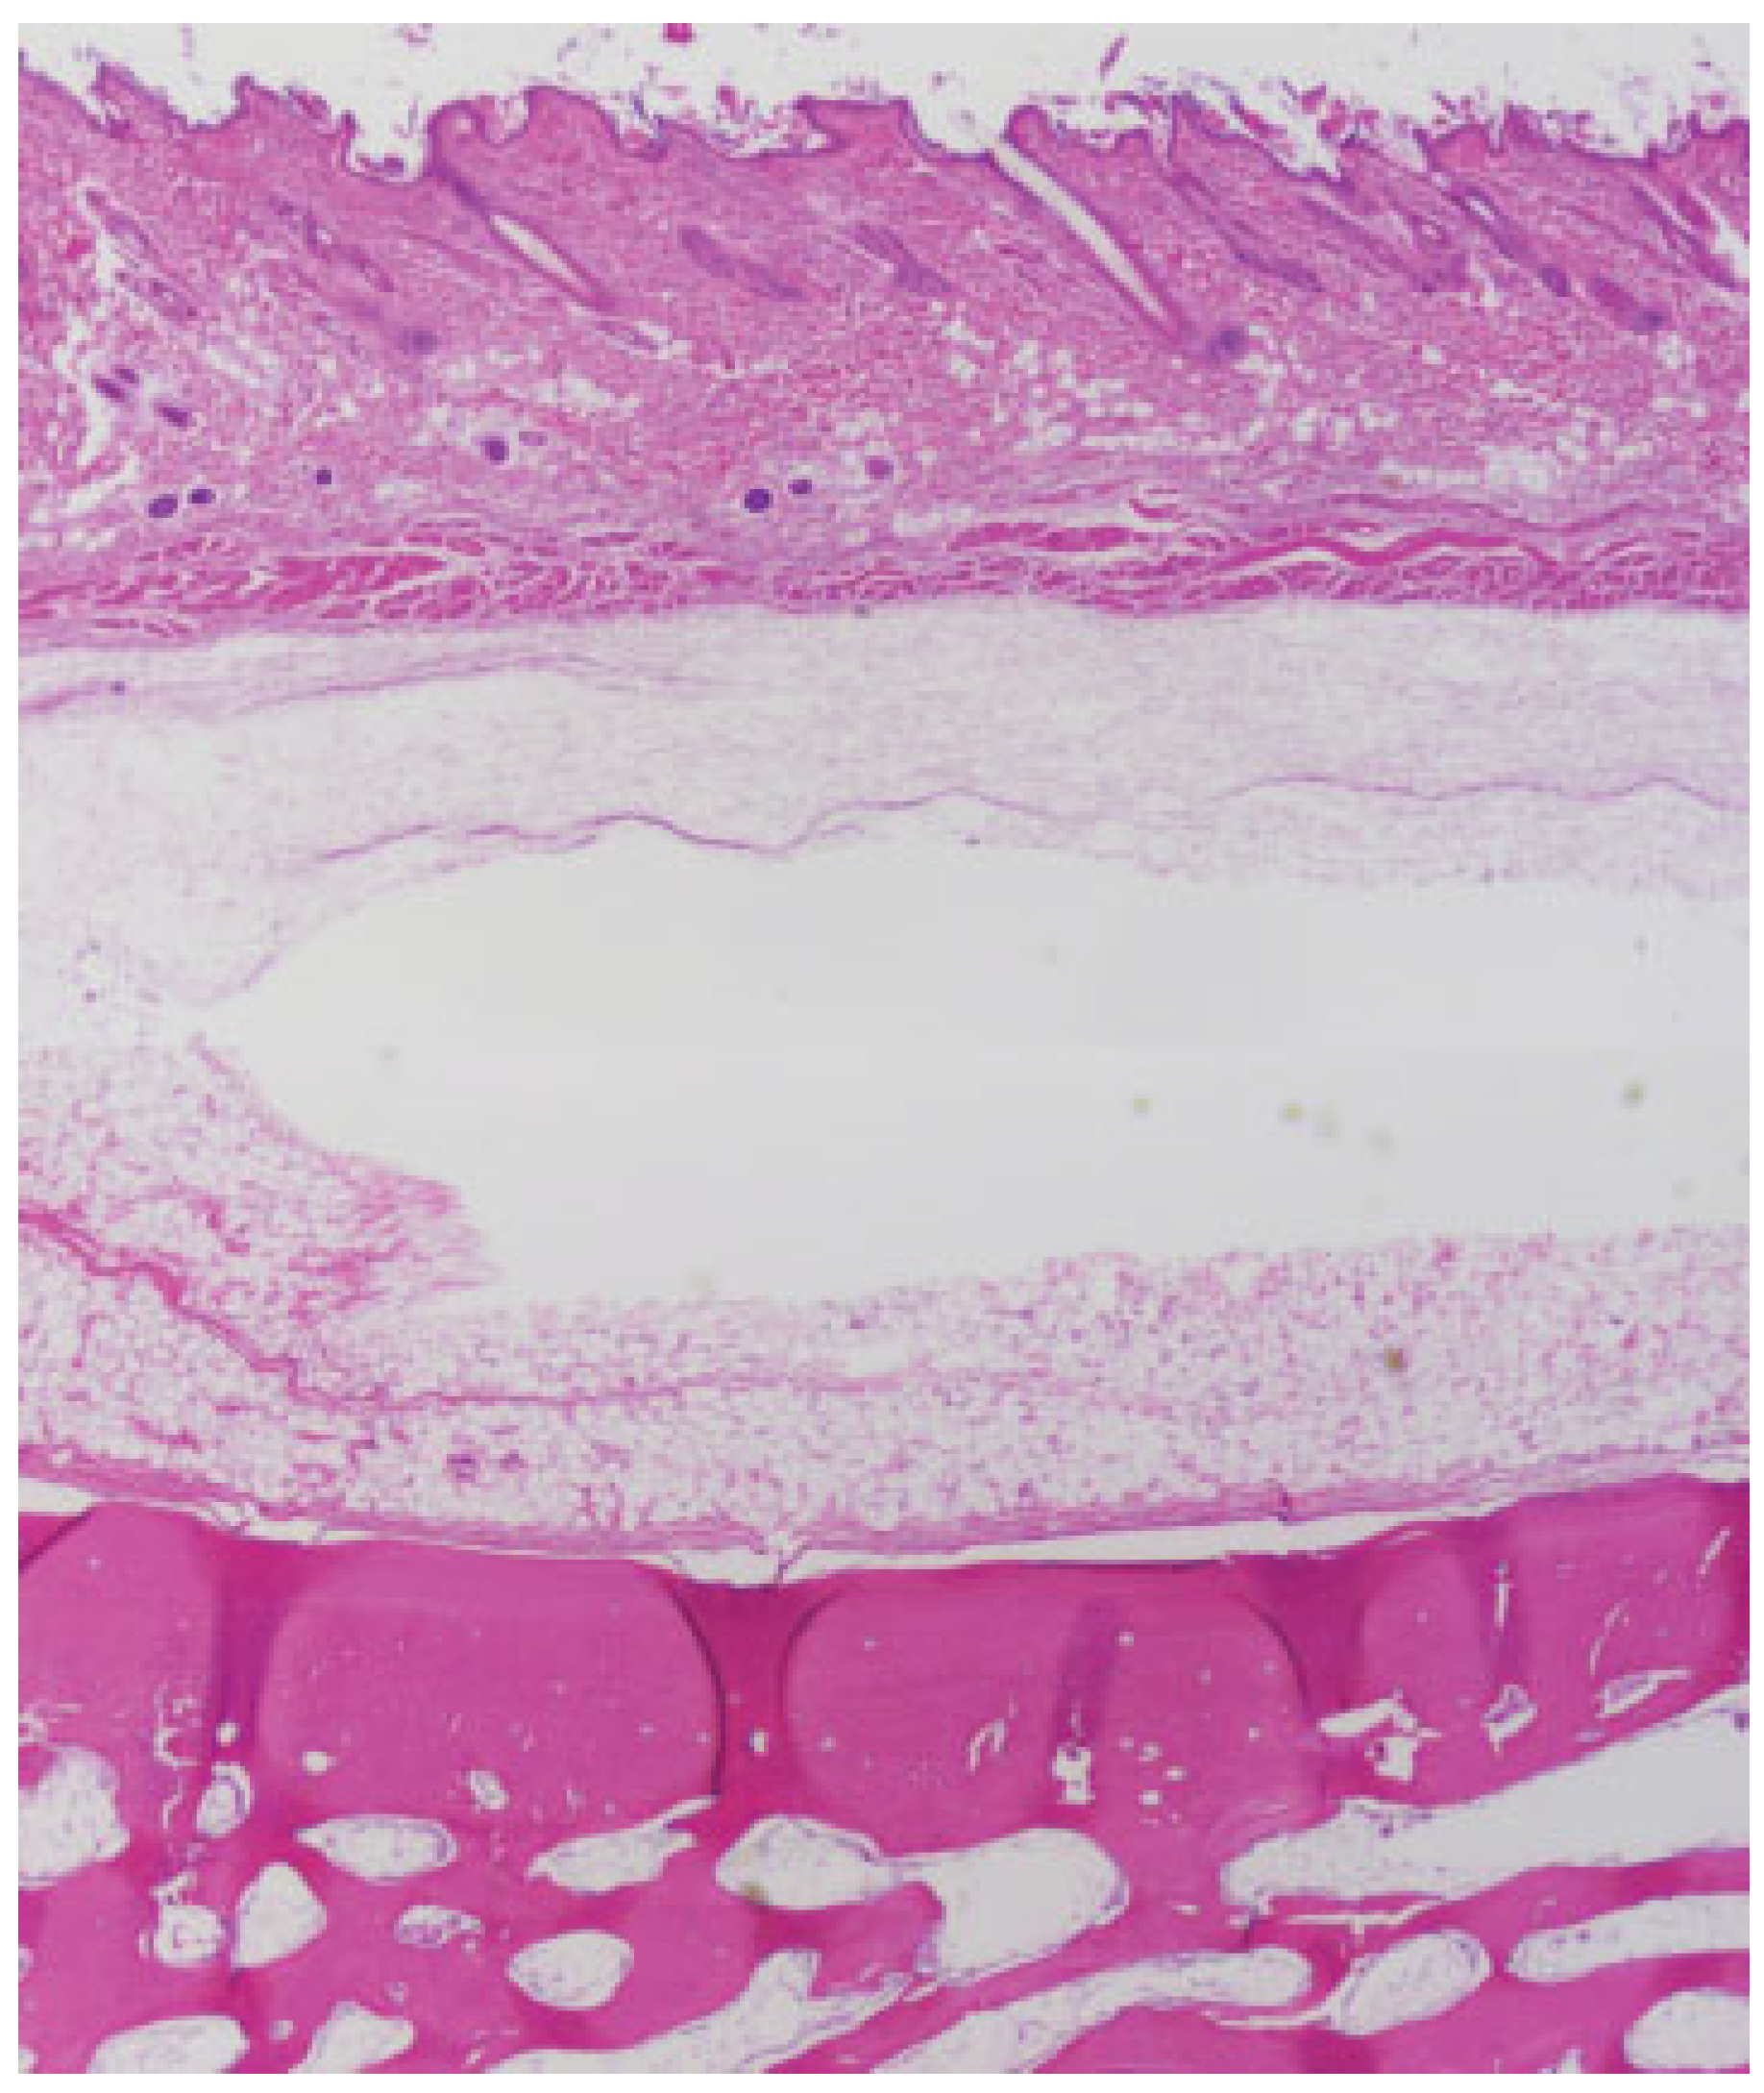

Figure 5.

Poly(D/L)lactide acid plate at 6 months postimplantation No residual implant material was noted. Some dermal fibrosis was noted in the soft tissue of the scalp, due to scarring from prior surgical incision. Underlying calvarial bone was unremarkable. (light microscopy, hematoxylin and eosin stain, original magnification ×40).

Figure 6.

Poly(D/L)lactide acid plate at 6 months postimplantation demonstrated focal foreign-body reaction (left, light microscopy, hematoxylin and eosin stain, original magnification ×100). At ×400 magnification (right), microscopic residual implant material was visible with surrounding giant cells. Note that this reaction was contained within the fibrous capsule surrounding the implant. The surrounding connective tissue was unremarkable.